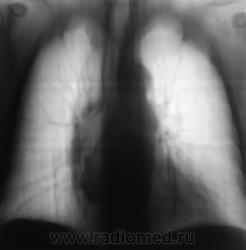

Рентгенограмма в прямой стандартной проекции.

похоже в просет "что-то" растет, наверное показана бронхоскопия? А дополнительная тень не ушко правого предсердия?

Хорошие томограмы, жаль нет бочка посмотреть вентиляцию нижней доли, а так конечно в просвете бронха дополнительная тень, предсердие бы оттеснило весь бронх. Надо рекомендовать бронхоскопию.